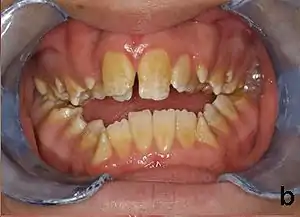

People with amelogenesis imperfecta may have teeth with abnormal color: yellow, brown or grey; this disorder can affect any number of teeth of both dentitions. Enamel hypoplasia manifests in a variety of ways depending on the type of AI an individual has (see below), with pitting and plane-form defects common.[4] The teeth have a higher risk for dental cavities and are hypersensitive to temperature changes as well as rapid attrition, excessive calculus deposition, and gingival hyperplasia.[5] The earliest known case of AI is in an extinct hominid species called Paranthropus robustus, with over a third of individuals displaying this condition.[6]

AI can be classified according to their clinical appearances:[18]

- Type 1 - Hypoplastic

- Enamel of abnormal thickness due to malfunction in enamel matrix formation. Enamel is very thin but hard & translucent, and may have random pits & grooves. Condition is of autosomal dominant, autosomal recessive, or x-linked pattern. Enamel differs in appearance from dentine radiographically as normal functional enamel.[19]